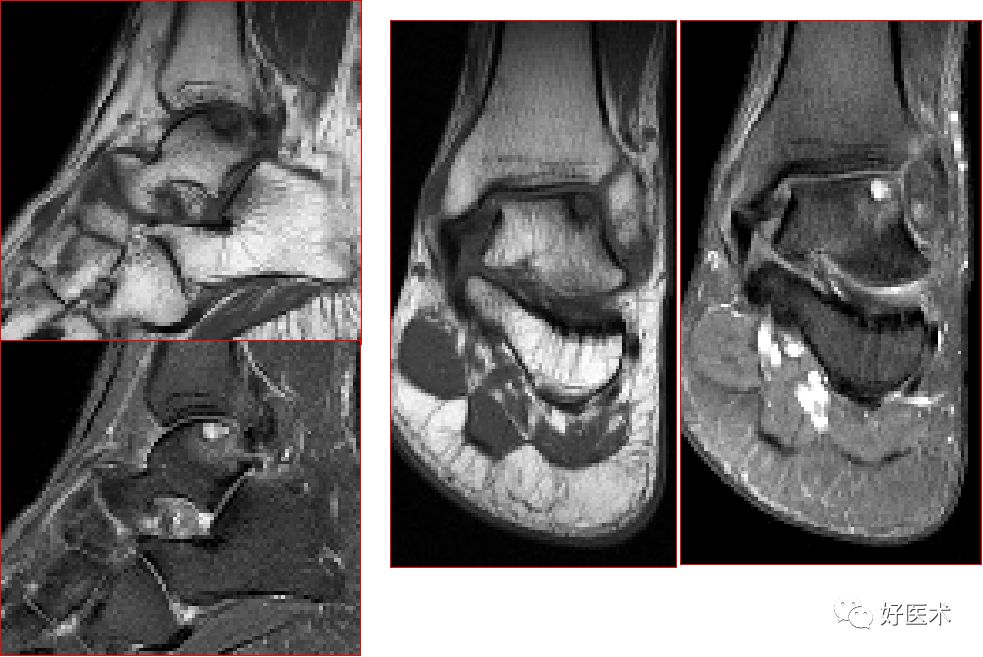

跟腱损伤

跟腱正常表现

跟腱运动损伤

跟腱附着处炎症

跟腱部分(完全)撕裂:跟腱最厚处前后径一般小于6mm,在踝关节上方2 – 6cm处跟腱纤维交叉走行,血液供应减少,易撕裂

慢性跟腱炎

跟腱炎症

慢性跟腱炎并跟腱部分撕裂

跟腱撕裂